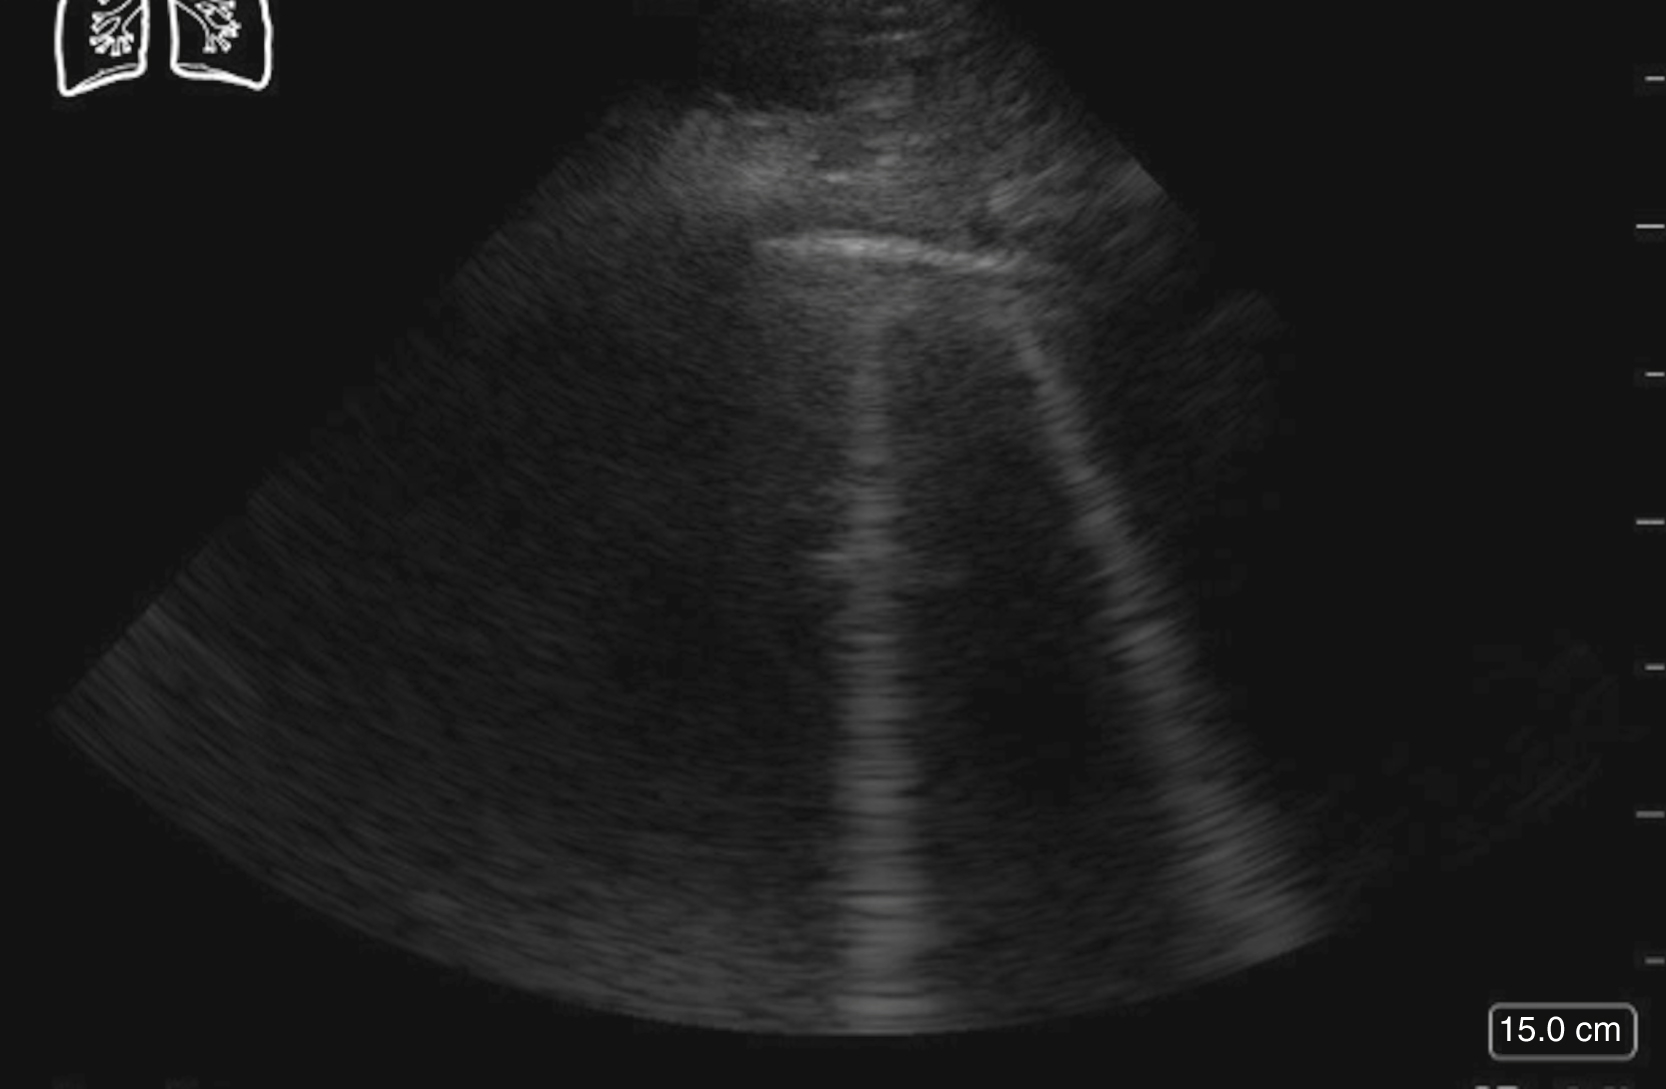

Image Acquisition

Using a low-frequency transducer (curvilinear or phased array) and significant pressure to displace the overlying bowel gas, the aorta should be visualized from the subxiphoid region to the umbilicus (bifurcation) in both transverse and longitudinal planes. The transverse view should be obtained first to avoid the cylinder tangent error, which could falsely underestimate the size of the aorta ( Fig. e3.7 and Video e3.6 ). Cross-sectional measurements should be taken of the aorta, outer wall to outer wall, including any mural thrombus that might be present. Aortic dissection may be detected by a combination of abdominal and cardiac scanning, with the addition of a suprasternal notch view to the traditional cardiac windows.

Fig. e3.7

Normal transverse view of the aorta.